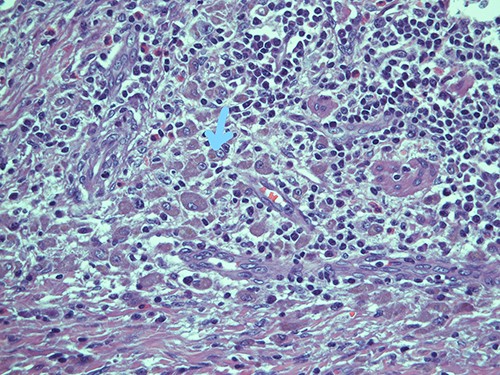

On microscopy, the appendix showed a thickening of his walls due to an accumulation of rounded elements with rich granular cytoplasm containing amorphous corpuscles and surrounded by microcalcifications, macrophage elements with adjacent de-epithelialized, ulcerated and eroded mucous tracts. No positive S100/pancytokeratin elements were found in the numerous sections examined. The morphological findings therefore indicated a form of malakoplakia (Figs 1–3), confirming its non-eptheliod and non-neoplastic nature (Fig. 4).

The most represented population is pancytokeratin negative, confirming its non-epitheliod and non-neoplastic nature; pancytokeratin, magnification ×10.